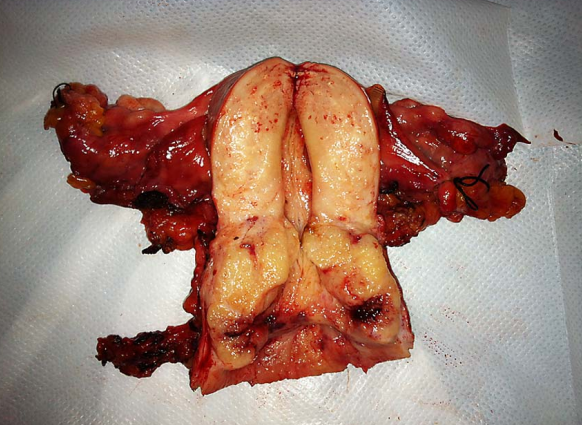

1.手术治疗 手术的优点是年轻患者可保留卵巢及阴道功能。主要用于早期子宫颈癌(ⅠA~ⅡA期)患者。①ⅠA1期:无淋巴脉管间隙浸润者行筋膜外全子宫切除术,有淋巴脉管间隙浸润者按ⅠA2期处理。②ⅠA2期:行改良广泛性子切除术及盆腔淋巴结切除术或考虑前哨淋巴结绘图活检(sentinel lymphnode mapping)。③ⅠB1期、和ⅠB2期ⅡA1期:行广泛性子宫切除术及盆腔淋巴结切除术或考虑前哨淋巴结绘图活检,必要时行腹主动脉旁淋巴取样。④部分ⅠB2期和ⅡA2期:行广泛性子宫切除术及盆腔淋巴结切除术和选择性腹主动脉旁淋巴结取样;或同期放、化疗后行全子宫切除术;也有采用新辅助化疗后行广泛性子宫切除术及盆腔淋巴结切除术和选择性腹主动脉旁淋巴结取样。未绝经、<45岁的鳞癌患者可保留卵巢。要求保留生育功能的年轻患者,ⅠA1期无淋巴脉管间隙浸润者可行子宫颈锥形切除术(至少3cm阴性切缘);ⅠA1期有淋巴脉管间隙浸润和ⅠA2期可行子宫颈锥形切除术加盆腔淋巴结切除术或考虑前哨淋巴结绘图活检,或和ⅠB1期处理相同;一般推荐ⅠB1期行广泛性子宫颈切除术及盆腔淋巴结切除术或考虑前哨淋巴结绘图活检,但若经腹或腹腔镜途径手术,手术指征也可扩展至ⅠB2期。

从左至右依次为Ⅰ、Ⅱ、Ⅲ及Ⅳ型子宫切除术的范围 Ⅰ型即筋膜外子宫切除术标本

Ⅲ型即广泛子宫切除术标本 盆腔淋巴结切除术标本

广泛子宫颈切除术切除的子宫颈及宫旁组织 广泛子宫颈切除术后功能重建的子宫及双附件